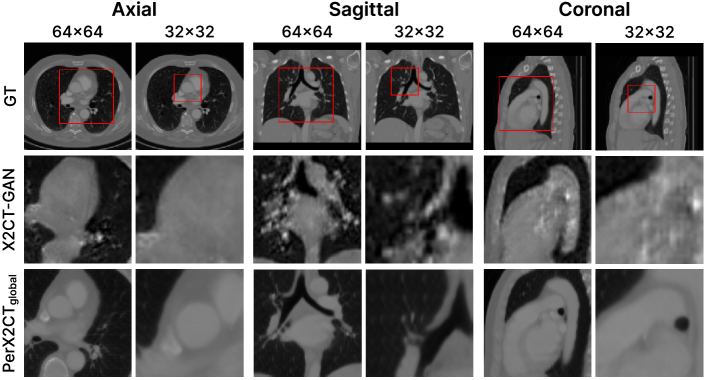

Refer to caption

Figure 3: Qualitative results of CT reconstruction.

Figure 4: Qualitative results for partial reconstruction. The red bounding boxes denote the target patches for reconstruction, which have 64×64646464\times 64, and 32×32323232\times 32 resolutions.

In Figure 3, we compare the visual quality of our proposed model and the baselines. Figure 3 shows that our reconstruction quality outperforms all baselines for all three views: axial, coronal and sagittal. 2DCNN reconstructs a blurrier image since it uses only one input X-ray. X2CT-GAN learns the boundary for large organs but fails to reconstruct accurately. PerX2CT successfully reconstructs the details of small anatomies, such as the atrium and aorta, clarifying the boundaries of the organs at the same time. Figure 4 illustrates the visual quality of the partial reconstruction of PerX2CTglobalsubscriptPerX2CT𝑔𝑙𝑜𝑏𝑎𝑙\text{PerX2CT}_{global} and the baselines. We show our results for the selected part on the 64×64646464\times 64 and 32×32323232\times 32 resolution. The baseline results are cropping from the full-frame slice reconstructed by each model and then up-scaling to a full-frame resolution through bilinear interpolation. Unlike this, PerX2CTglobalsubscriptPerX2CT𝑔𝑙𝑜𝑏𝑎𝑙\text{PerX2CT}_{global} directly reconstructs the target part without interpolation. We simply achieve that by adding randomly cropped data at training without any model architecture change.